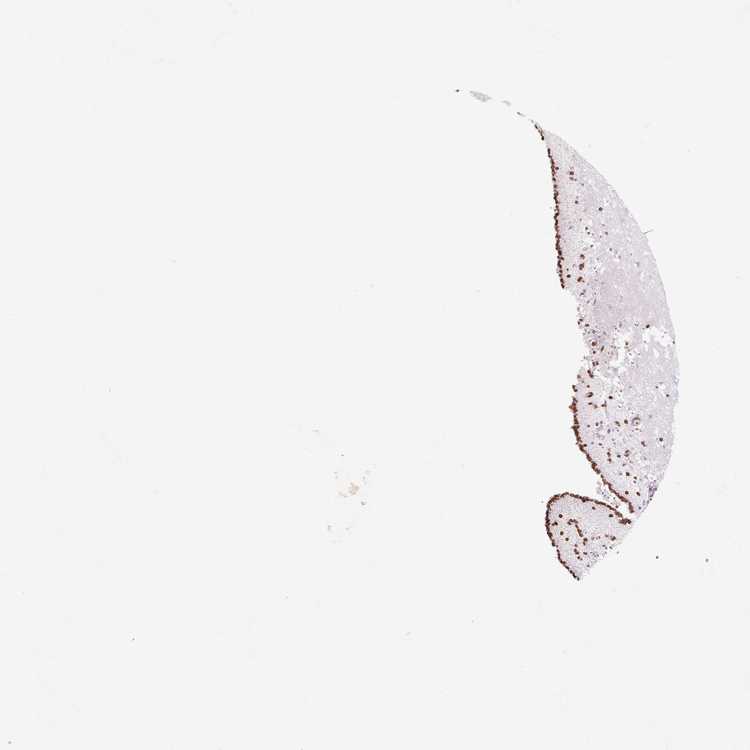

CAUDATE - Antibody stainingi

Antibody staining in the annotated cell types in the current human tissue is reported as not detected, low, medium, or high, based on conventional immunohistochemistry profiling in selected tissues. This score is based on the combination of the staining intensity and fraction of stained cells.

Each image is clickable and will lead to virtual microscopy that enables deeper exploration of all samples and also displays staining intensity scores, fraction scores and subcellular localization as well as patient and tissue information for each sample.

Antibody HPA050524Antibody CAB005269Antibody CAB079954

Glial cells HighHighLow

Neuronal cells HighHighNot detected